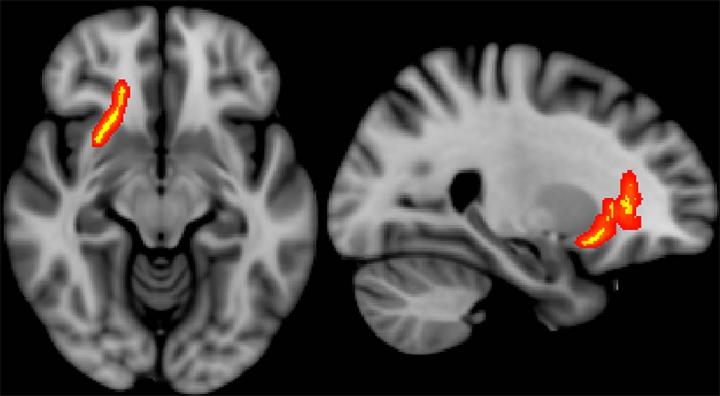

OAK BROOK, Ill. - Diffusion tensor imaging (DTI), a type of MRI, may be able to predict functional post-deployment outcomes for veterans who sustained mild traumatic brain injury (MTBI), or concussion, during combat, according to a new study published in the journal Radiology .

DTI uses measurements of water movement in the brain to detect abnormalities, particularly in white matter. Previous studies have linked DTI metrics to neurocognitive function and short-term functional outcomes in groups of patients. The desire to uncover possible long-term effects spurred Jeffrey B. Ware, M.D., from the Philadelphia VA Medical Center in Philadelphia, Pa., to evaluate combat veterans using this technique.

Dr. Ware and colleagues used brain MRI and DTI to study 57 military veterans who had a clinical diagnosis of MTBI upon return from deployment. The average length of time between injury and post-deployment evaluation was 3.8 years with an average follow-up duration of 1.4 years.

"All conventional MR images were interpreted as normal," Dr. Ware said. "We retrospectively analyzed the data from the DTI sequence to derive measures of white matter integrity, which we compared to clinical measures and subsequent outcome measures 6 months to 2.5 years after the initial evaluation."

The results showed significant associations between initial post-deployment DTI measurements and neurobehavioral symptoms, timing of injury, and subsequent functional outcomes. The measurements also correlated with greater healthcare utilization among veterans with MTBI.

Following initial post-deployment evaluation, 34 of the study participants returned to work. Veterans who did not return to work displayed significantly lower fractional anisotropy (FA) and higher diffusivity in a specific brain region, the left internal capsule. These measures imply less structural integrity in that area of the brain. As this region is known to contain important fibers providing motor stimulation to the typically dominant right side of the body, the results may provide a correlation between impairments in fine motor functioning and inability to return to work.

"Our findings suggest that differences in white matter microstructure may partially account for the variance in functional outcomes among this population. In particular, loss of white matter integrity has a direct, measurable effect," Dr. Ware said. "It was illuminating to see the association between measures of white matter integrity and important outcomes occurring months to years down the road in our study population."